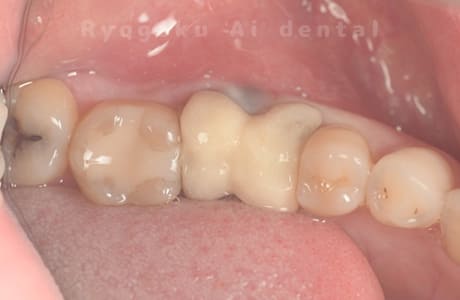

Case10

-

- 原因

- 右下6番 重度カリエス

- 治療内容

- 右下8を右下6へ移植に自家歯牙移植

- 治療期間

- 約1か月半

- 治療費用

- 220,000円

右下の銀歯が外れかかっているとのことでご来院された患者様です。虫歯が大きく、かつ歯が割れており、保存不可能と判断し、親知らずの移植を行いました。

<リスク・副作用>

治療後、痛みや違和感、出血、腫れなどが出る事があります。喫煙者、糖尿病などの方の場合、歯が生着しない場合があります。